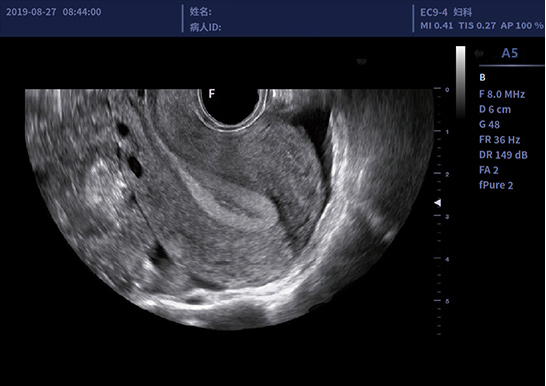

• EC9-4腔内探头

适用于经阴道、经直肠等

临床超声检查